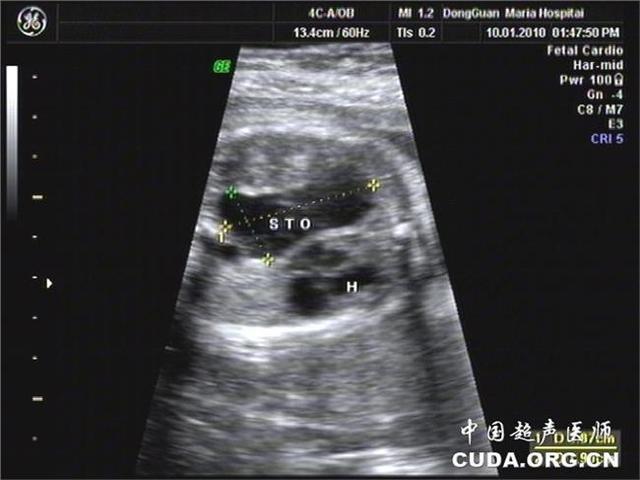

横膈膜是一张将胸腔与腹部分开并帮助呼吸的肌肉片。先天性膈疝是在横膈膜上有孔时发生的,因为它在子宫中没有正式形成。

横膈膜上有孔意味着腹部器官可以通过肌肉,挤压肺部,阻止肺部发育正常。孔可以出现在隔膜的任何一侧,但通常发生在左边。

先天性膈疝可在产前超声或婴儿出生后立即诊断出。